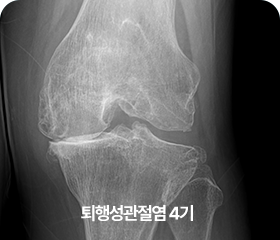

단계별 퇴행성 관절염 증상

4기